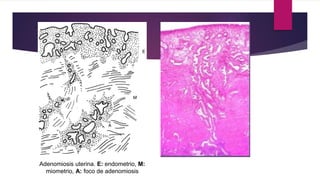

Adenomiosis uterina. E: endometrio, M:

miometrio, A: foco de adenomiosis

Adenomiosis uterina. E:endometrio, M: miometrio, A: foco de adenomiosis

ANATOMIA PATOLOGICA  Presenciade islotes endometriales (glándulas y estroma) en el espesor del miometrio.  Crecimiento del endometrio en profundidad  La unión endomiometrial es irregular y carente de una muscular de la mucosa  Generalmente se trata de endometrio basal, sólo ocasionalmente, de zona de tipo funcional

 Macroscópicamente losislotes se presentan como áreas ligeramente deprimidas, rosado amarillentas o pardas o de pequeños quistes con líquido pardo  El miometrio aparece hipertrófico  El cuerpo uterino es globuloso  La pared comprometida, engrosada